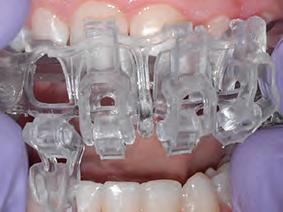

3D printed matrices: This is a relative newcomer in the US market, the 3M Filtek matrix (Fig. 7). It is a 3D-printed matrix based on a digital wax-up and is indicated to treat Class IVs, peg lateral incisors, diastema closures, and direct veneers. The clinician sends a digital or analog impression to the manufacturer indicating the purpose for construction, and the manufacturer creates a digital wax-up with proprietary design software. After the dentist approves the wax-up through a portal, the matrix is designed, printed and shipped to the clinician.

The clear matrix is tried on for fitting, removed for adhesive application, and then seated back and locked with a selflocking mechanism. The matrices have windows over every tooth to be restored and interproximal fins to prevent adjacent restorations from bonding together. The windows are then opened, and material is injected into the matrix through these windows. A flowable and a conventional viscosity composite can be used, allowing the traditional material to displace the flowable, aiding adaptation and ease of insertion. Another workflow is to place and cure a flowable composite at the

margins to help minimize the potential for voids, light curing, and inserting the conventional material. The windows are closed, and excess material is extruded through vents on the doors. The composite is polymerized through the clear matrix upon removal of the excess material. The composite does not bond to the matrix because the manufacturer coats the matrix with an isolating film.

From the authors’ point of view, this technique’s advantages include reproducing anatomical proximal contours well through the fins in the matrix. It allows treating multiple teeth at a time, and predictable results are obtained. Disadvantages include two appointments, the cost of the matrix, and, in some cases, the practitioner needing to produce the natural contours through contouring and polishing, which increases appointment duration.